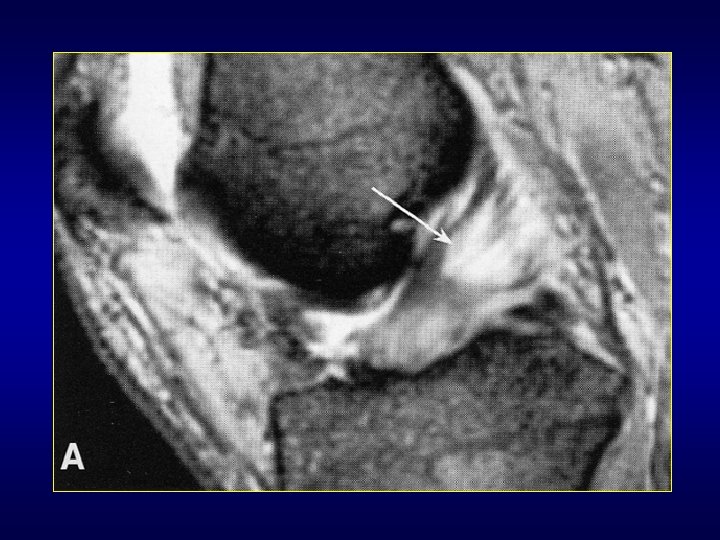

Les synovialosarcomes • Assez fréquents: 5 à 10% des T tissu mou • Adulte jeune • Région para-articulaire, proche gaine tendineuse, bourse synoviale, capsule • Membre inf: 60% (Cuisse et genou: 30%) • Masse + douleurs fréquentes • Rx et écho puis IRM +++ : limites, rapports avec tendons, capsule, gaines, bourses • Réhaussement signal en dehors zones nécrotiques et kystiques